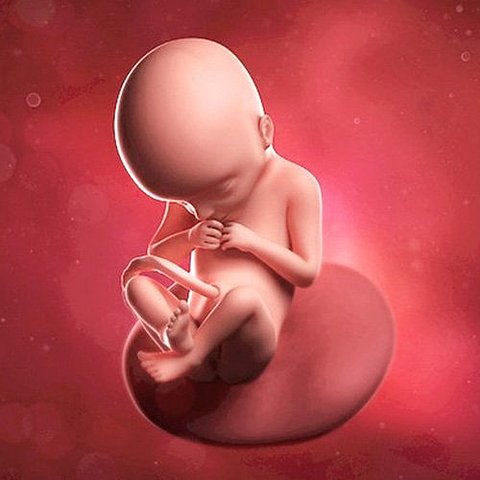

• Décima semana

Décima semana

Ahora ya se han formado todos sus órganos y están funcionando corazón, cerebro, hígado, riñones e intestinos. Irán creciendo y desarrollándose continuamente hasta el nacimiento pero ya es posible reconocerlos perfectamente definidos.

Mide entre 28 y 29 mm y pesa casi 5 gramos, comienza la formación de codos y rodillas. Esta semana es la última que se le llamará embrión, después pasará a ser feto. Ya se encuentra totalmente formado, ahora solo falta la maduración.